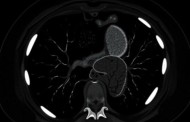

Расшифровка данных требует внимания. Врач оценивает индекс резистентности. Систолическая скорость важна для артерий. Если показатель высокой скорости, это хорошо. Обычно норма выше 30 см/с. Для вен важен отток. Заключение врача основано на цифрах.

Патология связана с диабетом. Уровень глюкозы влияет на сосуды полового органа. Поэтому диагностика патологии включает анализ сахара. Результаты исследования показывают наличие сбоя. Информативен метод при артериальных патологиях.

Диагноза недостаточно без цифр. Нужно провести сравнение. Кавернозные тела должны наполняться. Если нет, проблема с венами. Это влияет на лечения выбор.